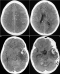

Image in medicine

The 11-year old girl presented a diagnosis of viral hepatitis A confirmed by anti-HVA IgM. Eight 8 weeks after, she developed hemorrhagic syndrome coupled with fever associated and persistent jaundice. The blood count showed aregenerative pancytopenia secondary to aplastic anemia confirmed by bone marrow biopsy. During conditioning for allogenic bone marrow grafts, the patient developed generalized seizures revealing disseminated intracerebral hemorrhage (pictures). There was a favorable outcome after blood transfusions and resuscitation. Hematological complications in hepatitis A are rare. Although intracerebral hemorrhage resulting from Hep A has never been reported in the literature; its occurrence is directly correlated with the degree of thrombocytopenia due to aplastic anemia. The prevalence of aplastic anemia in viral hepatitis is estimated at 0.1%. This complication implies systematic hematological evaluation in cases of viral hepatitis A; especially in severe forms or those associated with involving cholestasis.

Figure 1: cranial computed tomography scan showing disseminated intracerebral hemorrhage